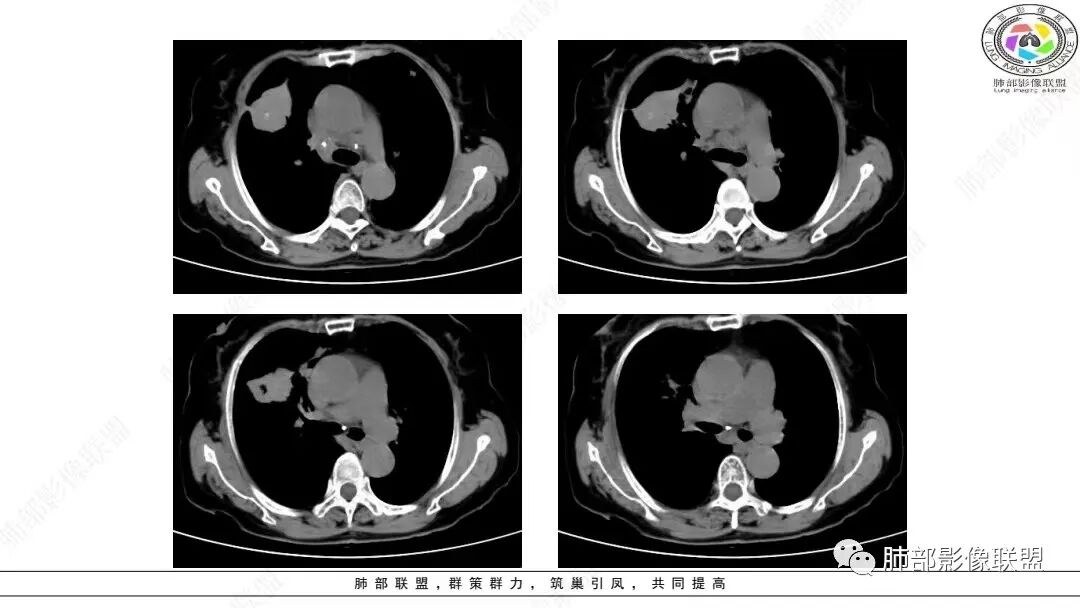

2.影像学特点:右肺上叶前段胸膜下不规则较大团块影,边界清楚欠光整,浅分叶,肺血管支气管出入,边缘膨隆胸膜凹陷具有一定张力,未见典型粗短毛刺,部分围以边界清楚的磨玻璃影,灶周小叶间隔增厚。块影密度不均,渐进性强化,可见砂砾样钙化,未见明显液化坏死或空洞。增强后病灶显示渐进性强化。MIP显示病灶内肺动脉穿行、并部分肺动脉受侵变细。纵隔及右锁骨上(胸廓入口)见肿大淋巴结。两肺可见多发大小不一的结节影,边界清楚,随机分布。

胸椎体溶骨性吸收破坏,突破骨皮质。腹部扫描未见肿块影。

本组97.13%病变累及胸膜,大部分病灶(75.41%)与纵隔关系密切,表现为靠近肺门或紧贴纵隔胸膜生长,多数病灶与纵隔胸膜之间有脂肪间隙存在。    111例(111/244,45.49%)显示“类胸膜尾征”改变,即肿瘤紧贴胸膜生长、增厚,但未突破胸膜向外生长,与正常胸膜的夹角呈钝角,在纵隔窗上呈现类似脑膜瘤的脑膜尾征样改变;推测其形成机制可能是肺LELC的生物学行为具有一定恶性,易侵犯胸膜,使胸膜增厚逐渐延伸,但其恶性度低于肺鳞癌、腺癌,较少直接导致胸膜不均匀增厚甚或突破胸膜向外生长。

本组50.82%(124/244)病灶周围见磨玻璃密度影改变,33.20%在磨玻璃密度影中伴有小叶间隔的间质增厚,表现为小叶间隔网格状增粗,但不伴有串珠状排列的小结节;其形成机制可能是肿瘤周围实质及间质均伴有大量淋巴细胞浸润以及小叶间隔的淋巴管扩张,而肺腺癌或鳞癌的癌性淋巴管炎多表现为小叶间隔结节状增厚,可呈串珠状改变。上述征象可作为肺LELC与肺鳞、腺癌的鉴别点。